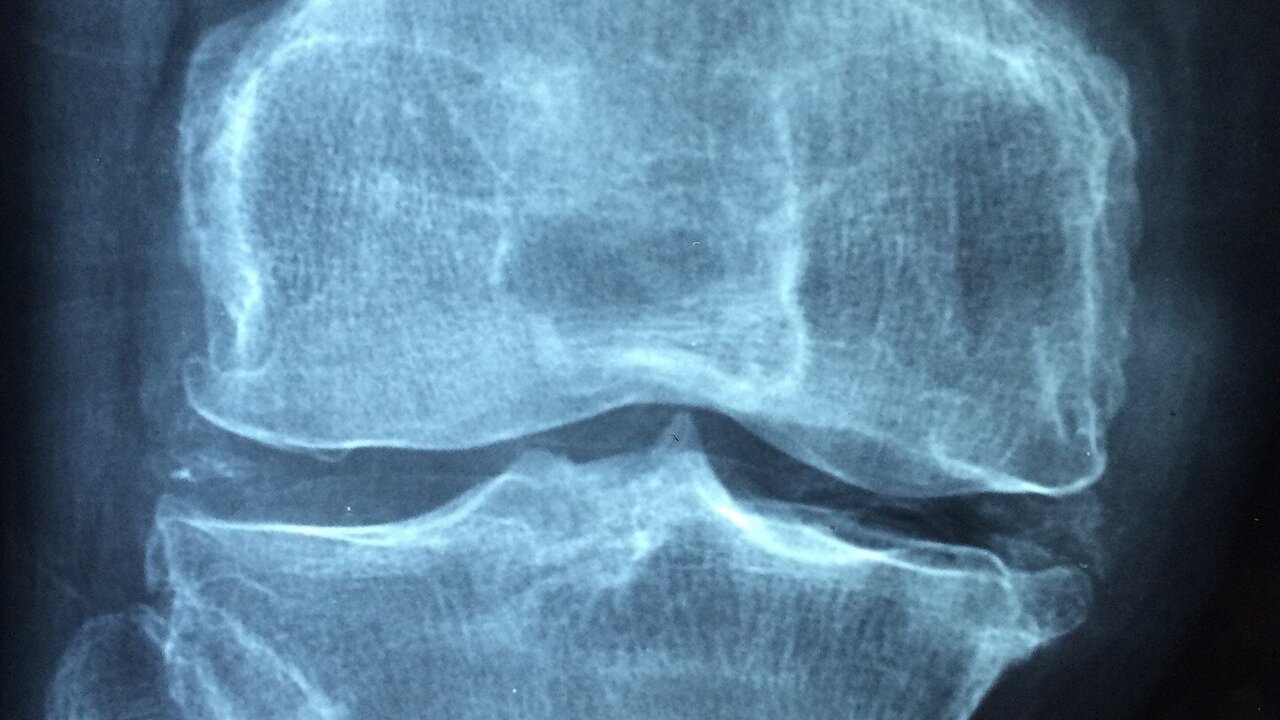

Osteoporosis is more common in women. It is also the main cause of disability in older women. White and Asian women entering menopause are most at risk.

Our bones are constantly renewed, and this happens rapidly in youth. After 20 years, the process slows down, and the peak of bone mass occurs at 30 years. As we age, bone mass is lost faster than it builds.

It is also known that the development of osteoporosis is affected by calcium deficiency. With low calcium intake, bone density decreases, bone mass begins to be lost earlier and the risk of fracture increases. Men and women aged 18-50 should get 1,000 mg of calcium per day. When women reach the age of 50 and men 70, this amount increases to 1200 mg.